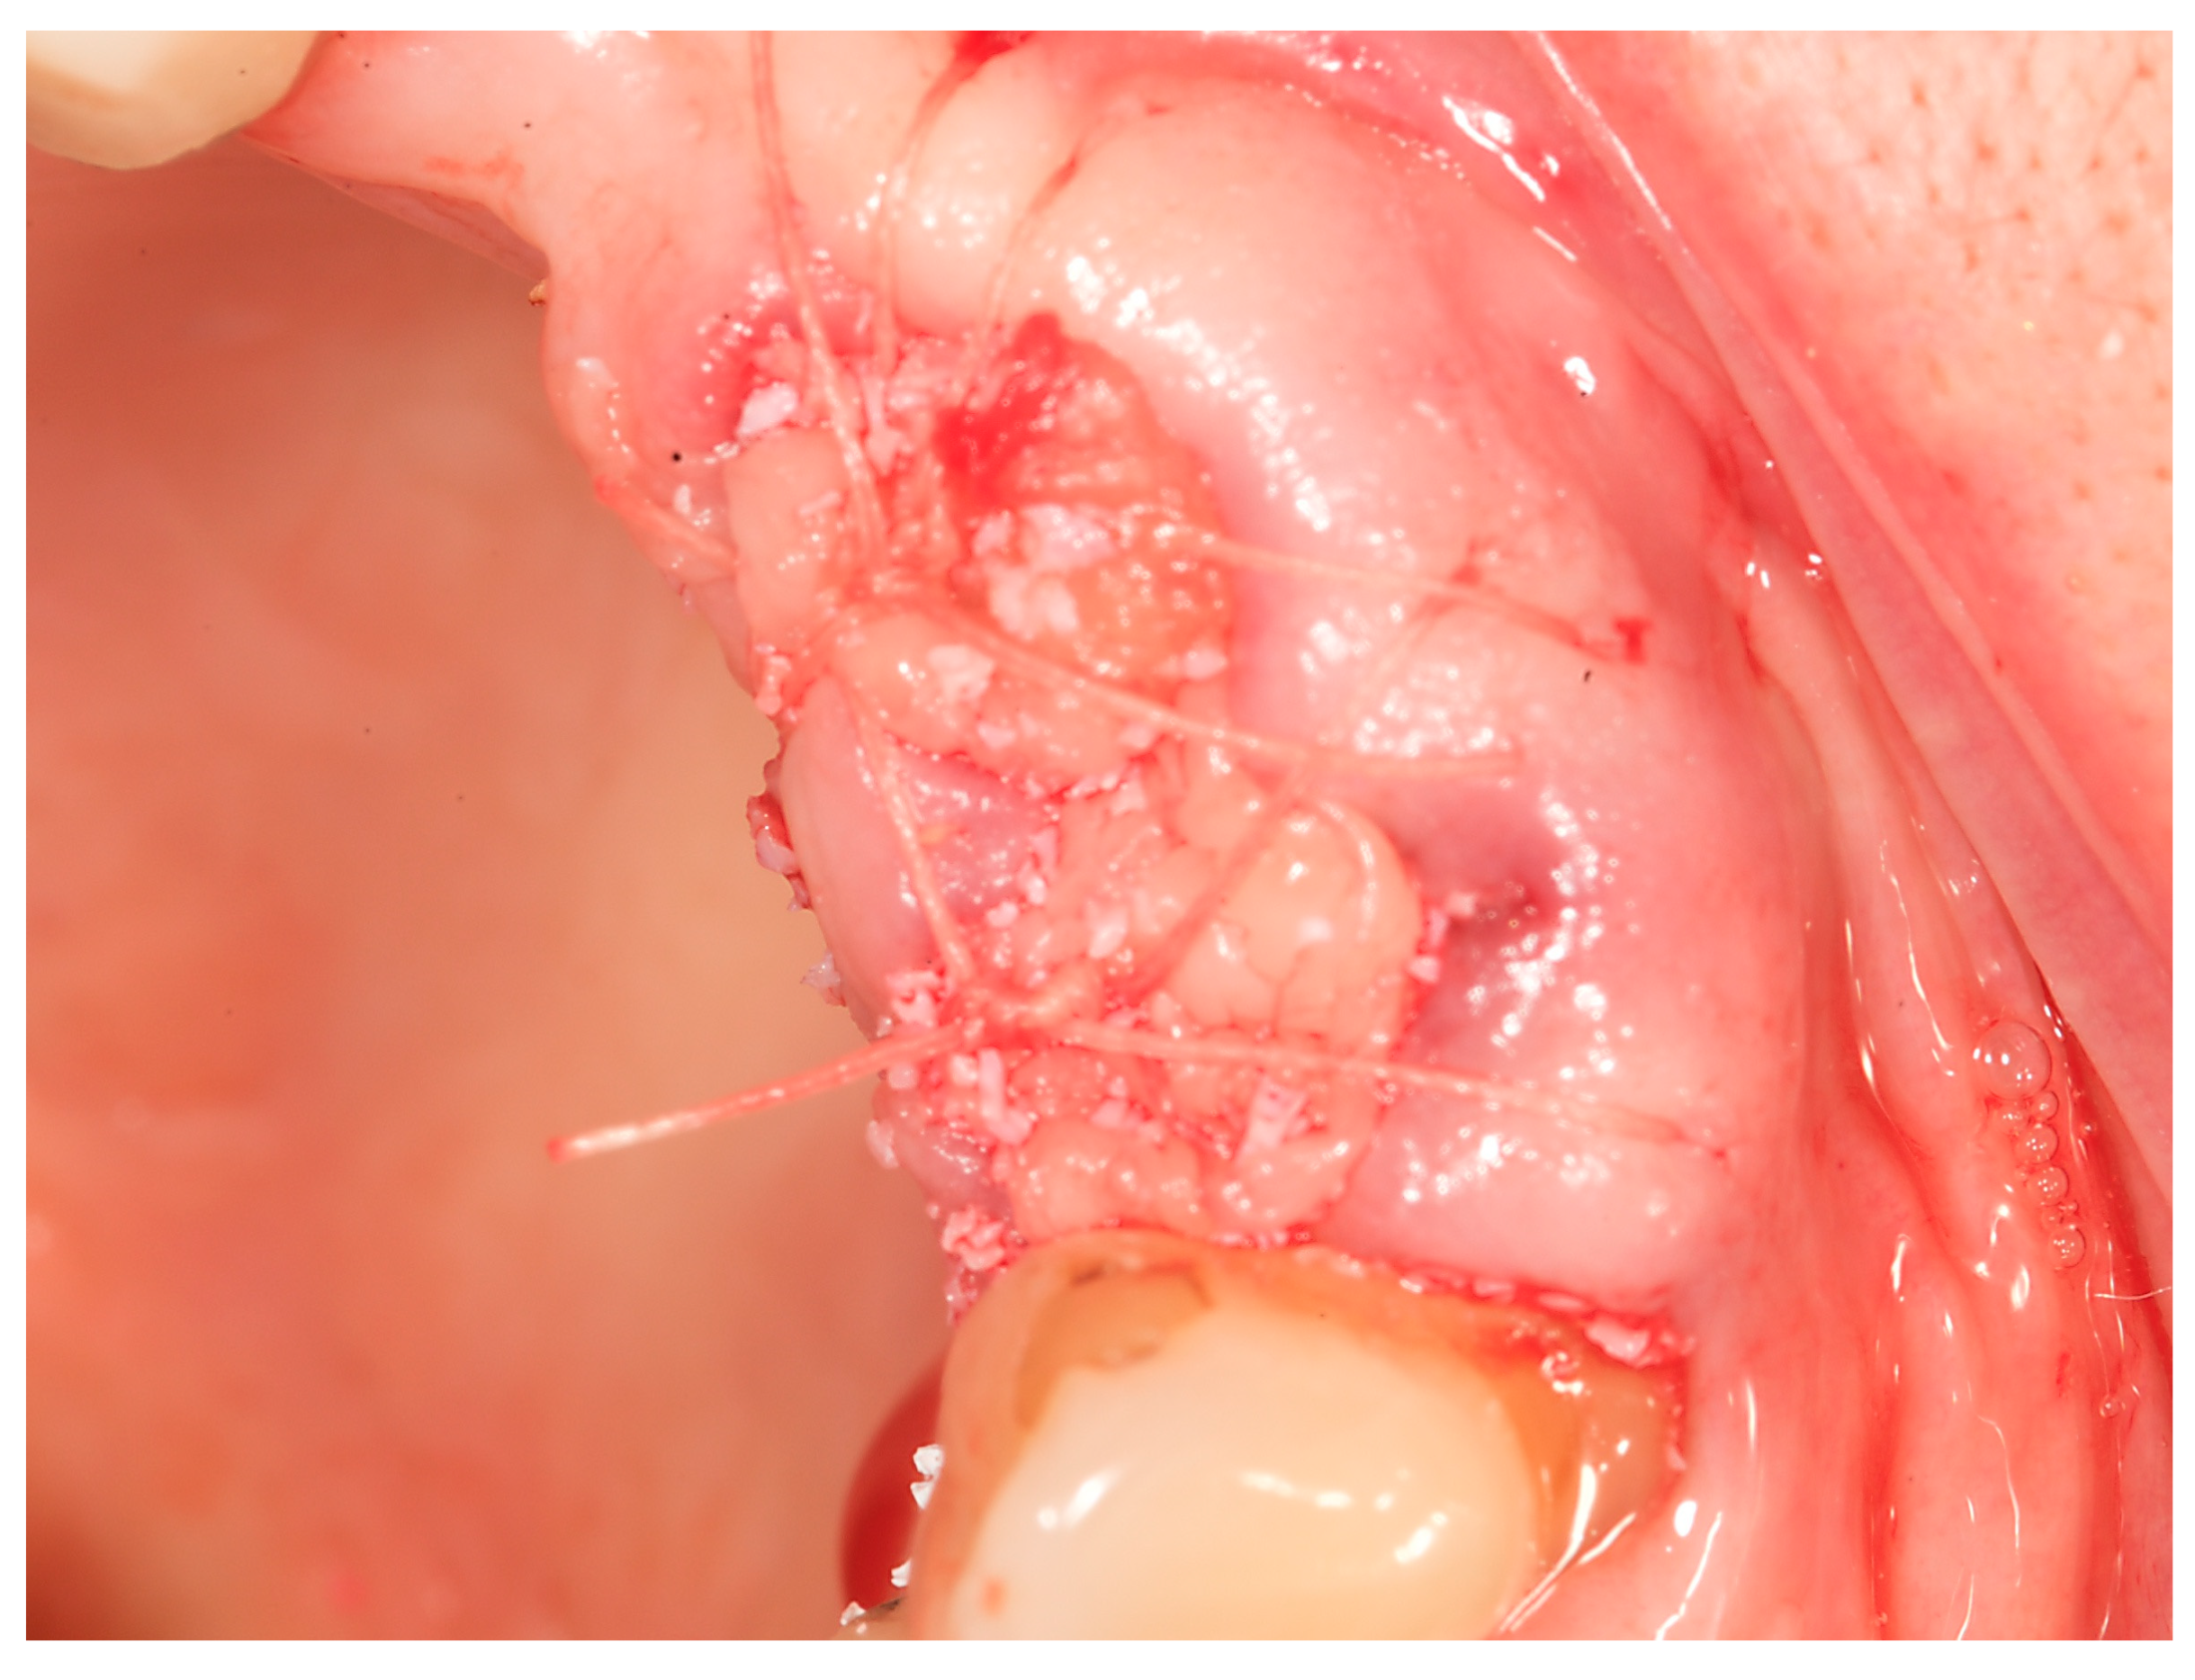

- Step 3: Teeth were removed using a minimally invasive extraction technique and the sockets were grafted with a xenograft and PRF

2.2. Alveolar Ridge Preservation Technique

3.1. Case Study 1

3.2. Case Study 2